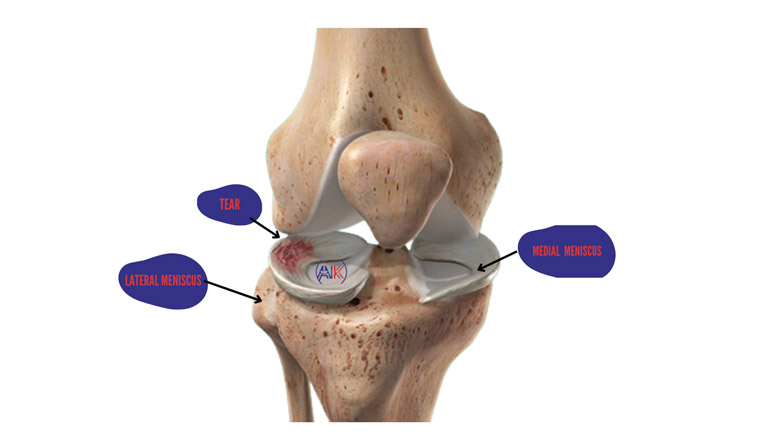

The meniscus, a C-shaped piece of cartilage located between your femur (thighbone) and tibia (shinbone) in each knee. There are two menisci in each knee—the medial meniscus on the inside and the lateral meniscus on the outside. These structures help cushion the knee joint, distribute load during movement, and provide stability by preventing your bones from rubbing together.

Injuries to the meniscus can occur during activities that involve twisting or rotating the knee, especially when the foot is planted on the ground.

Common causes include sports injuries, accidents, or degenerative changes in the knee and when the meniscus is torn. It can cause pain, swelling,stiffness, and difficulty moving the knee.